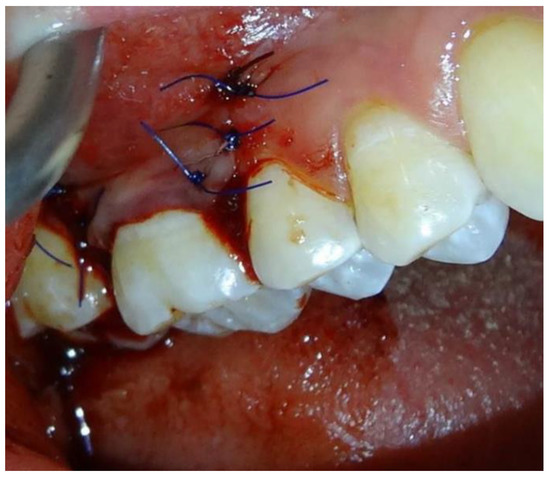

2.1.4. Surgical Procedures

2.2. Post-Surgical Protocol